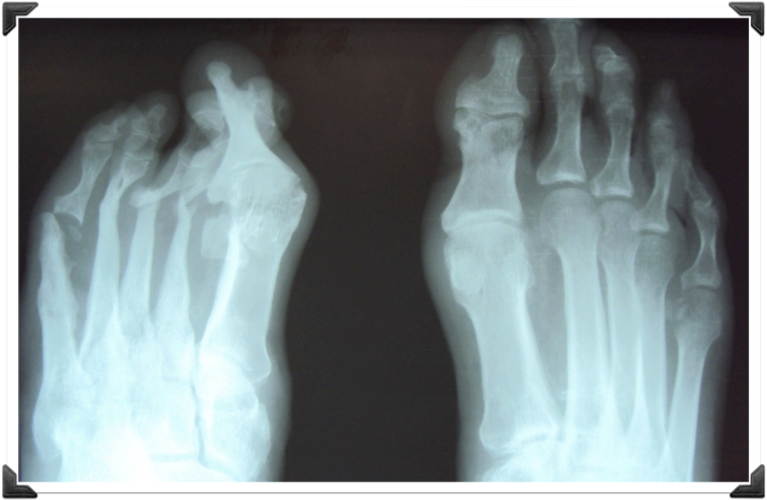

Rx Pre Operatorias

Cabeza del 2do MTT deformidad en flexion

Fusion Interfalangica de 2,3,4 y 5to Dedos

Dr. Luis Villanueva